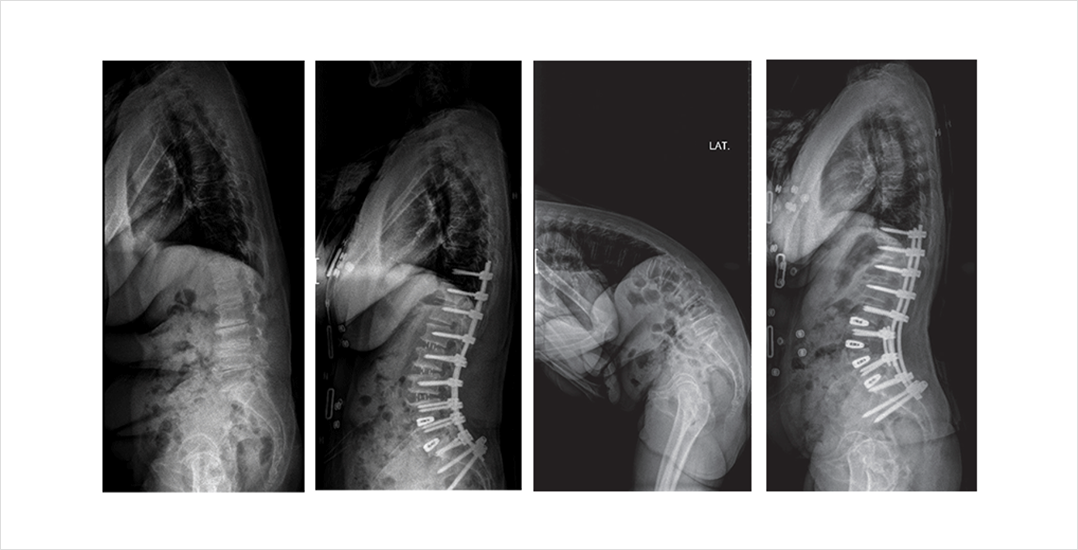

초기에는 소염진통제 등의 약물치료를 이용한 증상의 조절과 근육 강화 운동, 보조기 착용 등의 보존적 치료가 도움이 될 수 있으나 대부분의 환자가 고령이어서 근위축이나 근섬유화가 많이 진행되어 그 효과는 미지수입니다. 후만의 정도가 심할 경우 보존적 치료로는 교정이 어려워 수술적 치료를 통해 후만 변형이 된 척추를 전만의 형태로 만들어주는 것이 도움이 됩니다. 변형교정 수술은 의사와 환자 모두에게 부담이 될 수 있으므로 신중한 결정이 필요합니다. 또한, 고령의 환자들인 경우가 많고 절골술이나 장분절의 고정술이 필요한 경우가 많으므로 전신마취를 통한 수술을 받을 수 있는 상태인지를 평가하고 합병증 발생 위험을 고려하여 수술을 결정하게 됩니다. 수술 이후에는 재활치료와 적절한 영양 섭취, 골다공증 관리, 입식 생활로의 생활 습관 교정과 운동을 꾸준히 하는 것이 도움이 됩니다.